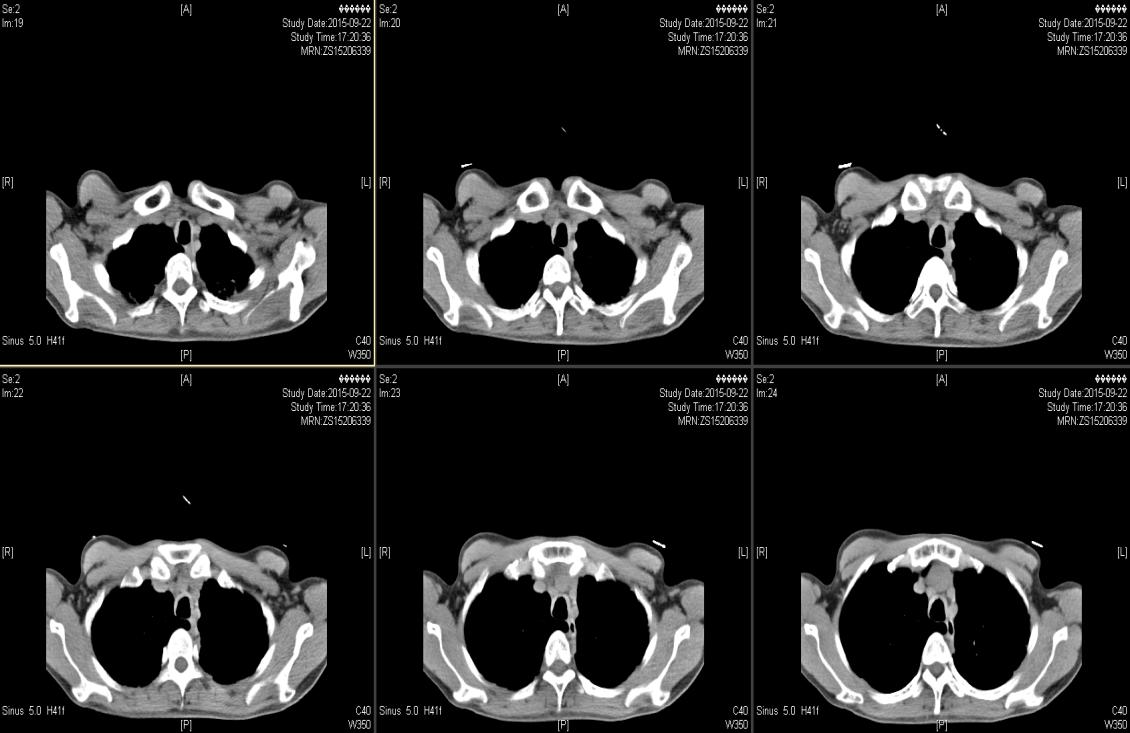

( 2015-9-22 ) 我院气管三维重建CT示 :气管、主支气管及其分支形态欠规则,管壁见明显增厚,管腔内壁凹凸欠光整,肺门处支气管管壁明显增厚,可见少许钙化,肺门处支气管管腔局部狭窄,远端分支管腔扩张呈囊柱状。见图1—图4。

图1

图2

图3

图4